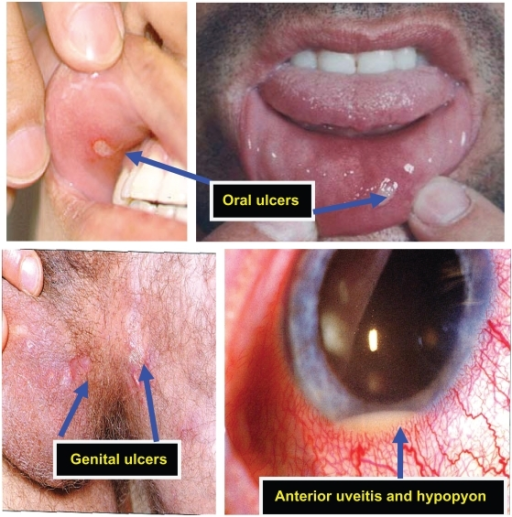

Behçet Syndrome

Behçet syndrome includes:

- Uveitis

- Genital ulcers

- Recurrent aphthous ulcers

An immune complex vasculitis of the tiny vessels is what causes Behçet syndrome.

Behçet syndrome can cause recurrent aphthous ulcers.